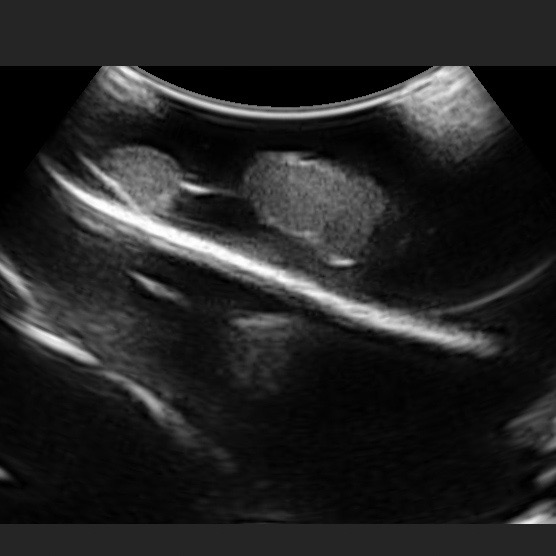

Pulse delved into the root of the client’s challenge and discovered it was beneficial for their client’s clinical trainers to show complications outside of bleeding and lesions, fatty and cirrhotic liver pathologies. When faced with multiple disease states, Pulse MDM does what we always do, design a pathology sampler, of course. We created a 3-piece liver, the left portion representing the fatty liver, the center portion being cirrhotic, and the right portion having hidden lesions that are only detectable by ultrasound. The lesions are planned to be penetrated by a probe, so over time it will require the replacement of just that portion of the model.

When it came to figuring out the liver color, the problem was not achieving the right color, but understanding what was the exact color of a fatty liver. We settled on beigey-yellow. The second issue was trickier: our shop ultrasound unit produced different results than the client’s hospital unit, which produced different results from the portable units our client purchased for their team to take on the road. Once we figured that out, the execution was easy. We have 35 years of model-making experience under our belt and are confident we can overcome almost any challenge.

Our soft three-piece liver includes snap features to easily remove the lesion portion for replacement. The model sits on a branded base that creates a professional presentation while providing anatomical context. The lower left portion of the fatty liver is resected and includes a puncture. A laceration on the cirrhotic portion serves to replicate a defect on a rough area. There are several lesions of varying sizes and shapes on the right. All these pathologies provide a platform for HCPs to learn which situations to use our client’s biosurgery products, and our client’s main goal was to help customers learn which product to use in each situation. The client is now able to meet specific customer needs that specialize in liver (HPB) surgery.

Microwave ablation is a heat-based thermal ablation modality that can treat hepatic malignancies. Microwaves can generate very high temperatures in very short periods, potentially leading to improved treatment efficiency and larger ablation zones. With microwave ablation, the surgeon inserts a small laparoscopic port or open incision to access the tumor. A CT scan or ultrasonic guidance is used to pinpoint the location of the tumor. A probe that emits microwaves is then inserted into the tumor. The probe produces intense heat that ablates (destroys) tumor tissue, often within 10 minutes. Microwave ablation has a number of advantages when compared to traditional radio frequency ablation including the following: